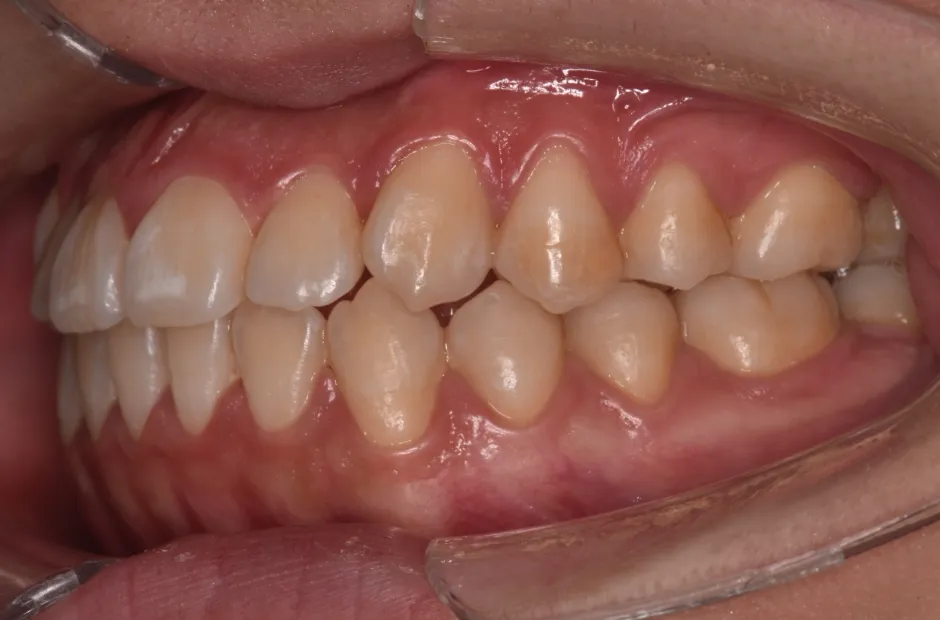

叢生

| 診断名・主訴 | 叢生 |

|---|---|

| 年齢・性別 | 43歳・女性 |

| 治療期間・回数 | 2年7か月 27回 |

| 治療に用いた主な装置 | 舌側矯正 |

| 抜歯部位 | 両顎4,4 |

| 治療費 | 100万円(税抜) |

| リスク・副作用 | 装置による違和感・疼痛・歯肉退縮・歯根吸収・虫歯のリスクなど |

治療前

治療中

治療後